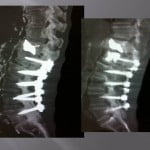

Vertebroplasty techniques in the case of lytic mestastatic lesions or myelomatic with pejorative invasion of the anterior or posterior walls.

The tumoral extension at the posterior wall with or without epidural inflammation constituted a few years ago a counter-indication to vertebroplasty. The experience of conventional radiology teams allowed to progressively reaching that limit. Numerous precautions are necessary to avoid complications.

In case of lytic tumoral lesion invading the posterior wall.

The major risk is compression of the spinal roots by the cement. An excellent radio-opacity of the cement is fundamental to perfectly limit its position and its diffusion under continuous scopic control.

We position the trocar at the level of the most anterior portion of the tumor and cross the adjacent bone. We slowly inject a few drops of cement at the level of the vertebrae not invaded, then as the cement is getting more dense, we withdraw while injecting cement.

The lesion must be filled as much as possible. An bilateral entrance way can be very useful for an optimal filling. In case of a pedicular contact, the withdrawal of the trocar is performed slowly while injecting the rest of the very thick cement little by little to create a bone bridge under scopic guidance. The risk to reach nervous root is important by extension in the foramen, a perfect control of the move s compulsory to avoid nervous complications.